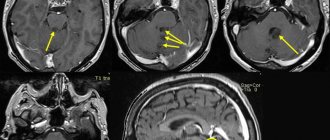

Обнаружение субкортикальной каверномы по изменениям поверхностной коры и оболочек

Удаление каверном коркового и субкортикального расположения, как правило, не представляет сложности. Краниотомию осуществляют по стандартной методике в проекции каверномы на свод черепа. У больных с поверхностно расположенными каверномами в половине случаев можно наблюдать более или менее выраженные изменения мягкой и арахноидальной оболочек, а так же поверхностных отделов коры в виде их желтой окраски. В отдельных случаях видна непосредственно ткань каверномы.

Энцефалотомию выполняют в месте максимального изменения мозгового вещества и оболочек мозга, либо в глубине ближайшей к каверноме борозды. Планирование доступа должно быть особенно тщательным при каверномах, расположенных в белом веществе полушарий и имеющих небольшие размеры. Ориентиры в виде изменения поверхности мозга в таких случаях, как правило, отсутствуют. В этих случаях необходимо использовать УЗ сканирование, при необходимости – нейронавигацию. При невозможности обнаружить каверному после 1 — 2 энцефалотомий операцию лучше прекратить, так как дополнительная травма мозга может привести к развитию неврологических дефектов. Удаление каверномы может быть выполнено вторым этапом после уточнения локализации образования.